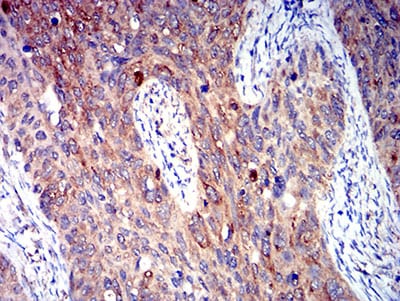

分类: 科研抗体货号: 31313别名: TR; HTR; CF2R; PAR1; PAR-1应用: IHC反应种属: Human